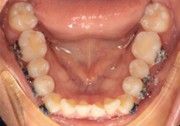

The IOS Mini Cinch Back Plier demonstrated superior control and a significantly reduced risk of bracket debonding and wire deformation compared to the regular Hammerhead plier from a different brand. Wire bends achieved with the IOS Mini Cinch Back Plier maintained integrity even under high-torque activation. The following images illustrate key differences in bend quality, wire distortion, and proximity to the bracket between the IOS Mini Cinch Back Plier and the conventional Hammerhead plier.